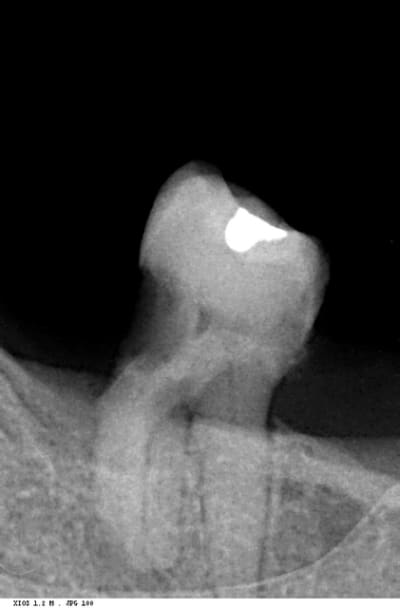

Hier, extration de prevue sur cette 37 sur ce patient de 60 ans. Bien sur, la racine distale s'est petée lors de la mobilisation. Impossible d'aller la recuperer. J'ai essayé de fraiser autour pour avoir une accroche au bernard et elevateur en tout genre mais pas moyen. J'ai pas insisté,, ne voulant pas fraiser l'os pendant 15 km mais ca commence à m'embeter ce genre de situation. vous avez des astuces? Merci

oui radio pas top (patient obese avec plancher bien haut). Mais je vois pas ce que peut nous apporter l'apex mesial vu que j'ai reussi a sortir cette racine mesiale

racine a gauche=racine distale=racine qui est resté dans l'os. Ca s'est cassé du à la carie

racine a droite de l'image=racine mesiale=celle qui est venue avec le davier

On devine la branche montante a gauche de l'image.

racine gauche, je ne vois pas de ligament, alors qu'il devrait être très large.

Le ciment peut à certains endroits être soudé à l'os.

Avant même de commencer, je sais à 90% que ce morceau restera en place.

Perso, je vois deux racines en distal... Une séparation des deux et un ptit coup de fraise (zekrya chir ou autre) en distal aurait sans doute permis de les extraire plus facilement.

Le ligament, je le vois en mesial de la racine distale mais pas en distale de cette racine. Mais ca doit etre du à l'angle de vu

Sinon ce qui me fait chier, c'est que j'ai l'impression de voir une lesion peri apicale sur cette derniere

oui quand meme, la racine mesiale, le ligament fait 10 km de large. Je sais que je suis pas doué en chir mais si je suis pas capable de sortir ca, c'est alarmant

Non je parle donc bien de la racine de gauche (distale) qui semble dedoublé et infecté. Ca a cassé direct à la prise au davier lié à l'enorme carie qui l'a surplombe